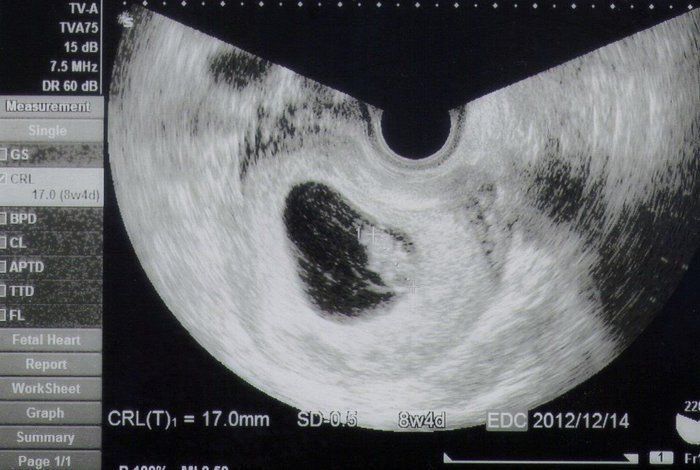

Tomomiさんの妊娠8週目のエコー写真 ついに産婦人科へ転院

妊娠3カ月目に突入し、初めての産婦人科へ。里帰りまでの約半年お世話になりました。

初めて心音を聞かせてもらい、震えるほど感動しました。「ドクドクざわざわ」、一生懸命生きている命の音を聞き、「ママもしっかりしなくちゃ」と背筋が伸びました。

母子手帳交付の許可も降り、4年目の結婚記念日に最高のプレゼントを貰いました。